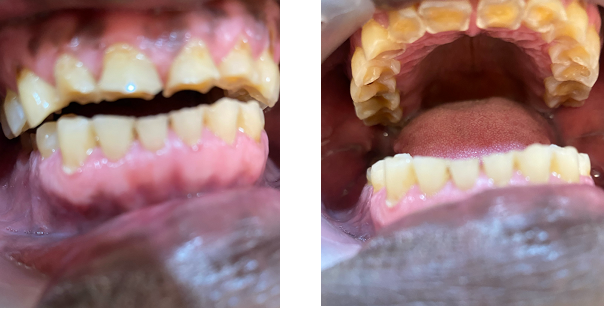

The BRUXi index, a tool proposed by Orthlieb and Duminil was used to determine the intensity of bruxism [24]. The BRUXi index is a score obtained from elements collected during the interview and clinical examination. The value of the index is obtained by adding the BRUXiq score (score obtained via the self-questionnaire) to the BRUXiex score (score obtained by collecting information in the clinical assessment). BRUXi = BRUXiq + BRUXiex. The intensity of sleep bruxism was defined as follows: low bruxism = BRUXi<20; moderate bruxism: 20<BRUXi<30 (Figure 1) and severe bruxism: BRUXi≥30 (Figure 2).